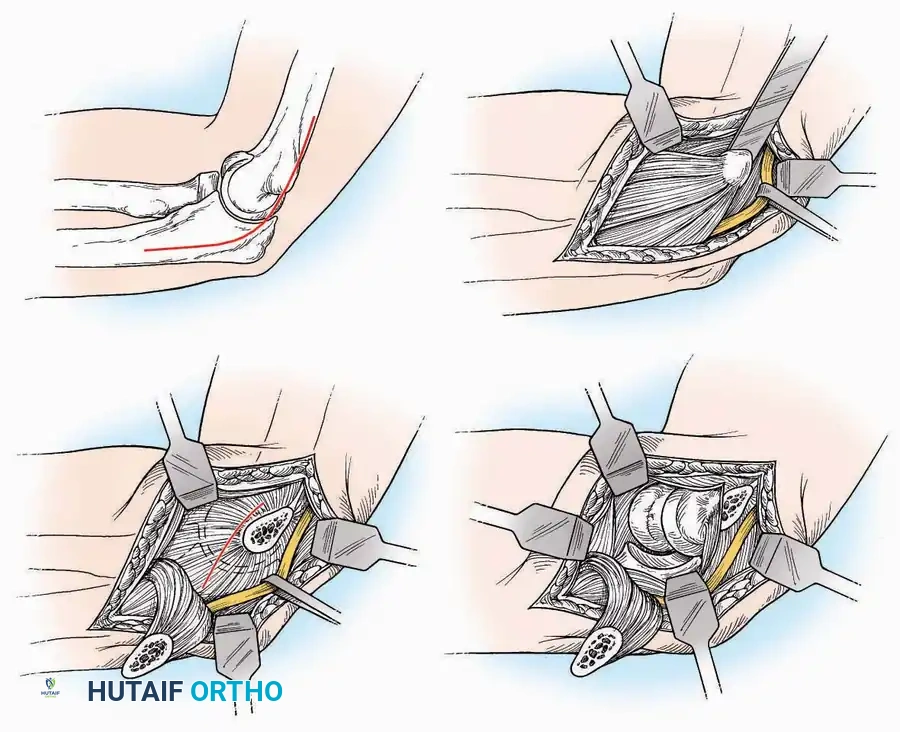

Anterior Approach

Indications: Total ankle arthroplasty (TAA), anterior ankle arthrodesis, and excision of anterior tibial/talar osteophytes (anterior impingement).

💡 Clinical Pearl

Gaining access to the medial gutter (the articulation between the medial malleolus and the medial articular facet of the talus) can be challenging through a pure anterior approach. Meticulous medial subperiosteal dissection of the joint capsule is required to avoid excessive traction on the anterior neurovascular bundle.

Surgical Technique:

* Incision: Make a 10 to 15 cm longitudinal incision over the anterior aspect of the ankle, centered exactly midway between the medial and lateral malleoli.

* Superficial Dissection: Incise the superficial fascia. Identify and protect the superficial peroneal nerve branches laterally and the saphenous nerve medially.

* Internervous Plane: The deep dissection exploits the plane between the Extensor Hallucis Longus (EHL) tendon (innervated by the deep peroneal nerve) and the Extensor Digitorum Longus (EDL) tendons (also innervated by the deep peroneal nerve).

* Neurovascular Bundle: Incise the extensor retinaculum. Carefully identify the anterior tibial artery and the deep peroneal nerve, which typically lie between the EHL and EDL, or directly deep to the EHL. Retract the neurovascular bundle laterally with the EDL, or medially with the EHL, depending on the specific anatomical variant encountered (lateral retraction is most common).

* Capsulotomy: Incise the anterior joint capsule longitudinally. Elevate the capsule subperiosteally from the anterior tibia and the talar neck to expose the entire tibiotalar articulation.